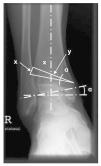

Figura 1. Planificación de la osteotomía. La siguiente operación permite calcular aproximadamente la altura de la base de la cuña que debe extraerse de la tibia: x = y x tan a. En la osteotomía, por tanto, se realizará probablemente una corrección de 1º para una resección de 1 mm (menor en correcciones más pequeñas).

Figura 2. CORA (centro de rotación y angulación): en las deformidades postraumáticas, deberá planificarse la osteotomía a la altura de la desviación del eje; de lo contrario se produciría una traslación de la porción distal con el correspondiente desplazamiento del eje mecánico de la articulación.